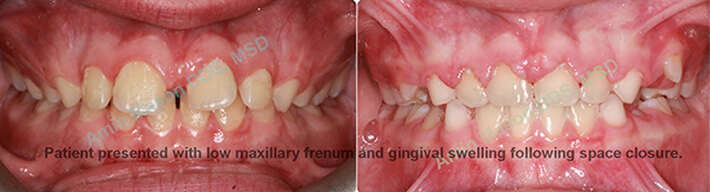

Removal Of Excess Gingiva and Low Frenum

We offer laser gum recontouring in Columbus to improve the appearance of your smile. The soft tissue diode laser used at Polaris Orthodontic Center uses a narrow beam of light energy, which can remove and reshape the gum tissue as needed. Healing time after the laser procedure is minimal, and no bleeding occurs. Dr. Mason has extensive experience in the use of diode lasers to correct gummy smiles, uncover partially erupted teeth for bracket placement, and reshape uneven gingival tissue.